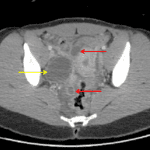

- Bilateral dilated fluid-filled structures in the pelvis

- Complex collection with internal septation in the expected location of the right ovary

- Moderate volume free fluid layering in the pelvis and small volume perihepatic ascites

- Pyosalpinx and tubo-ovarian abscess

Findings concerning for bilateral pyosalpinx and possible right tubo-ovarian abscess. Small volume perihepatic fluid could relate to associated perihepatitis (Fitz-Hugh-Curtis syndrome).